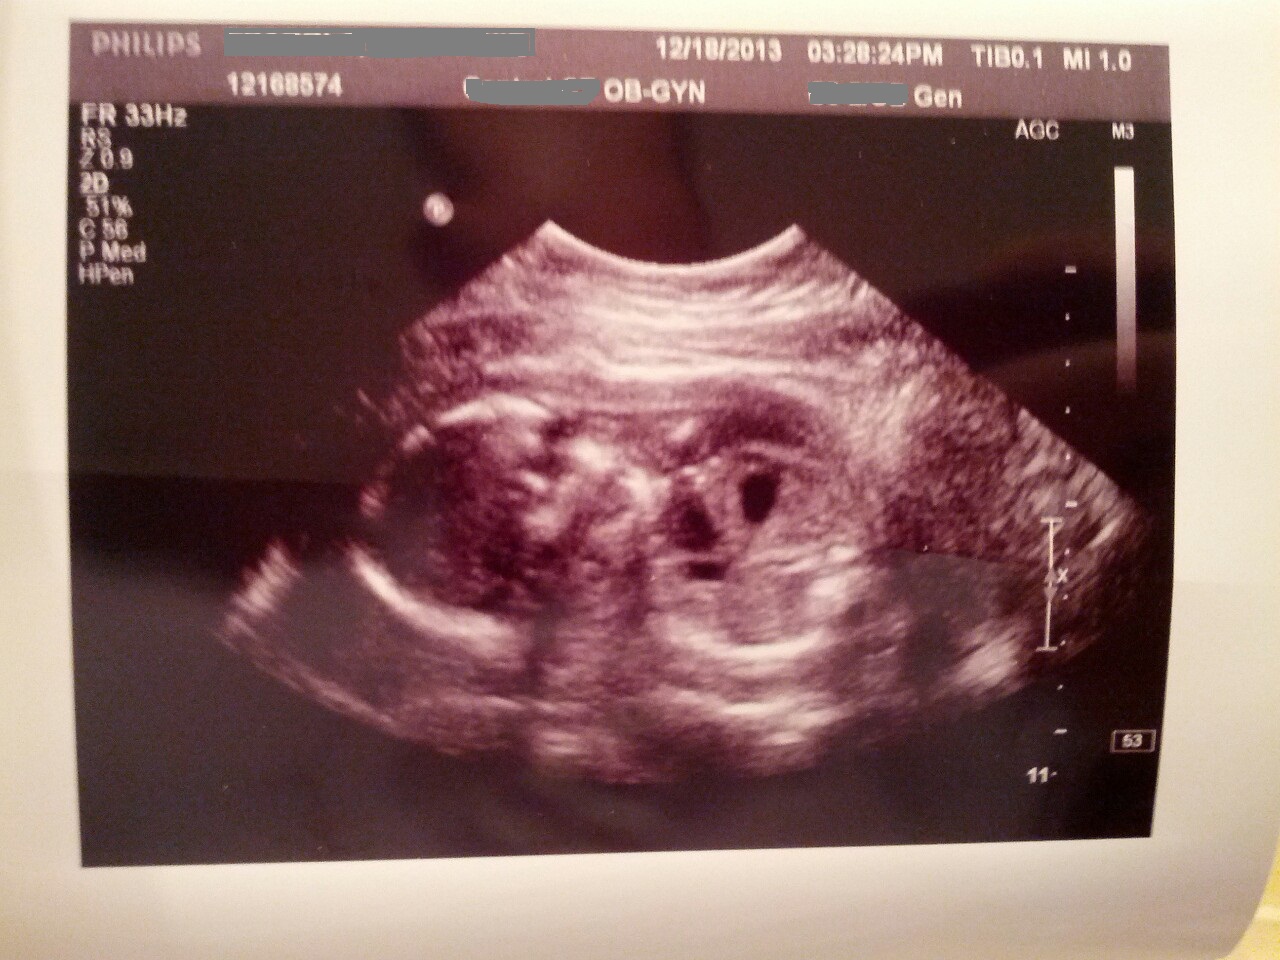

May 22, 2014 by Peter 5.22.14 – Throwback Thursday . Throwback Thursday. An oldie but a goodie Share this: Share on X (Opens in new window) X Share on Facebook (Opens in new window) Facebook Email a link to a friend (Opens in new window) Email Print (Opens in new window) Print Like Loading...